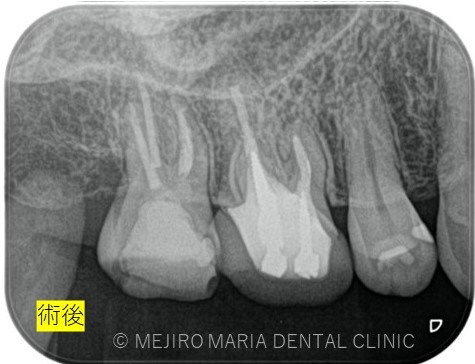

治療後の様子

治療回数は2回で終了しています。2回目の治療終了時には初診時で患者様が訴えていた違和感は改善され、次週、問題なければ仮歯の製作に移行する予定。

また、3ヶ月後には経過観察を行い根管治療の予後を確認する予定。